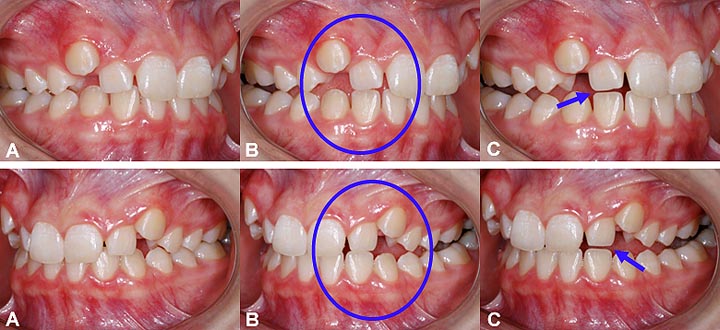

Exemple d’usure “fonctionnelle” chez une fille de 14 ans; (A) Les canines supérieures sont hautes et ne peuvent jouer leur rôle de protecteur pendant les mouvements de la mâchoire. (B) Lorsque la mandibule se déplace vers la droite (photos du haut) ou vers la gauche, les dents latérales entrent en contact et commencent à s’user. (C) En fin de mouvement, l’usure est visible sur le bout des incisives latérales qui sont déjà raccourcies. (Fille – 14 ans)